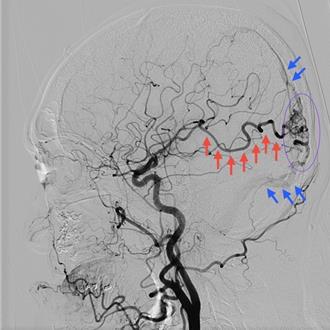

新竹68歲的王姓婦人患有高血壓,清晨被家人發現跌倒在家中浴室門口緊急送醫,經「急性腦中風區域聯防」機制,迅速將病人後送轉至東元綜合醫院繼續搶救,透過電腦斷層影像圖檢查,神經內科醫師蔡坤璋診斷為蜘蛛網膜下出血,當機立斷進行血管攝影檢查,抓出危及生命主因,發現婦人的前大腦交通動脈處藏有1顆動脈瘤且已破裂出血不止,醫療團隊迅速執行動脈瘤栓塞術,手術成功止血,順利救回婦人的寶貴生命。

台中64歲林姓男子日前在家突然感到劇烈頭痛,「像被雷打到」,幾分鐘內倒地昏迷,家人送他到衛福部豐原醫院急診,醫療團隊隨即啟動腦中風及腦出血急救流程,經電腦斷層檢查顯示患者罹患蜘蛛網膜下腔出血,主因是顱內動脈瘤破裂,神經外科與放射診斷科啟動複合式手術室,救回他一命。

南投縣45歲女子突然意識不清、左側肢體無力就醫,衛福部立南投醫院進一步檢查發現她罹患少見的「顱內動靜脈畸形」,由於她有肝硬化合併凝血異常,不宜開刀,轉往醫學中心使用伽馬刀治療。醫師建議,顱內動靜脈畸形若破裂出血恐喪命,若確診應定期追蹤治療。

知名配音員李小姐從事配音工作超過20年,長期日夜顛倒、高工時的工作型態,使她處於高度壓力與過勞狀態。某日她突然出現劇烈頭痛後陷入昏迷,家人緊急將她送至急診,經診斷為「顱內動脈瘤破裂」,若未及時治療,致死率高達5成以上,倖存者也常留下嚴重神經功能障礙。